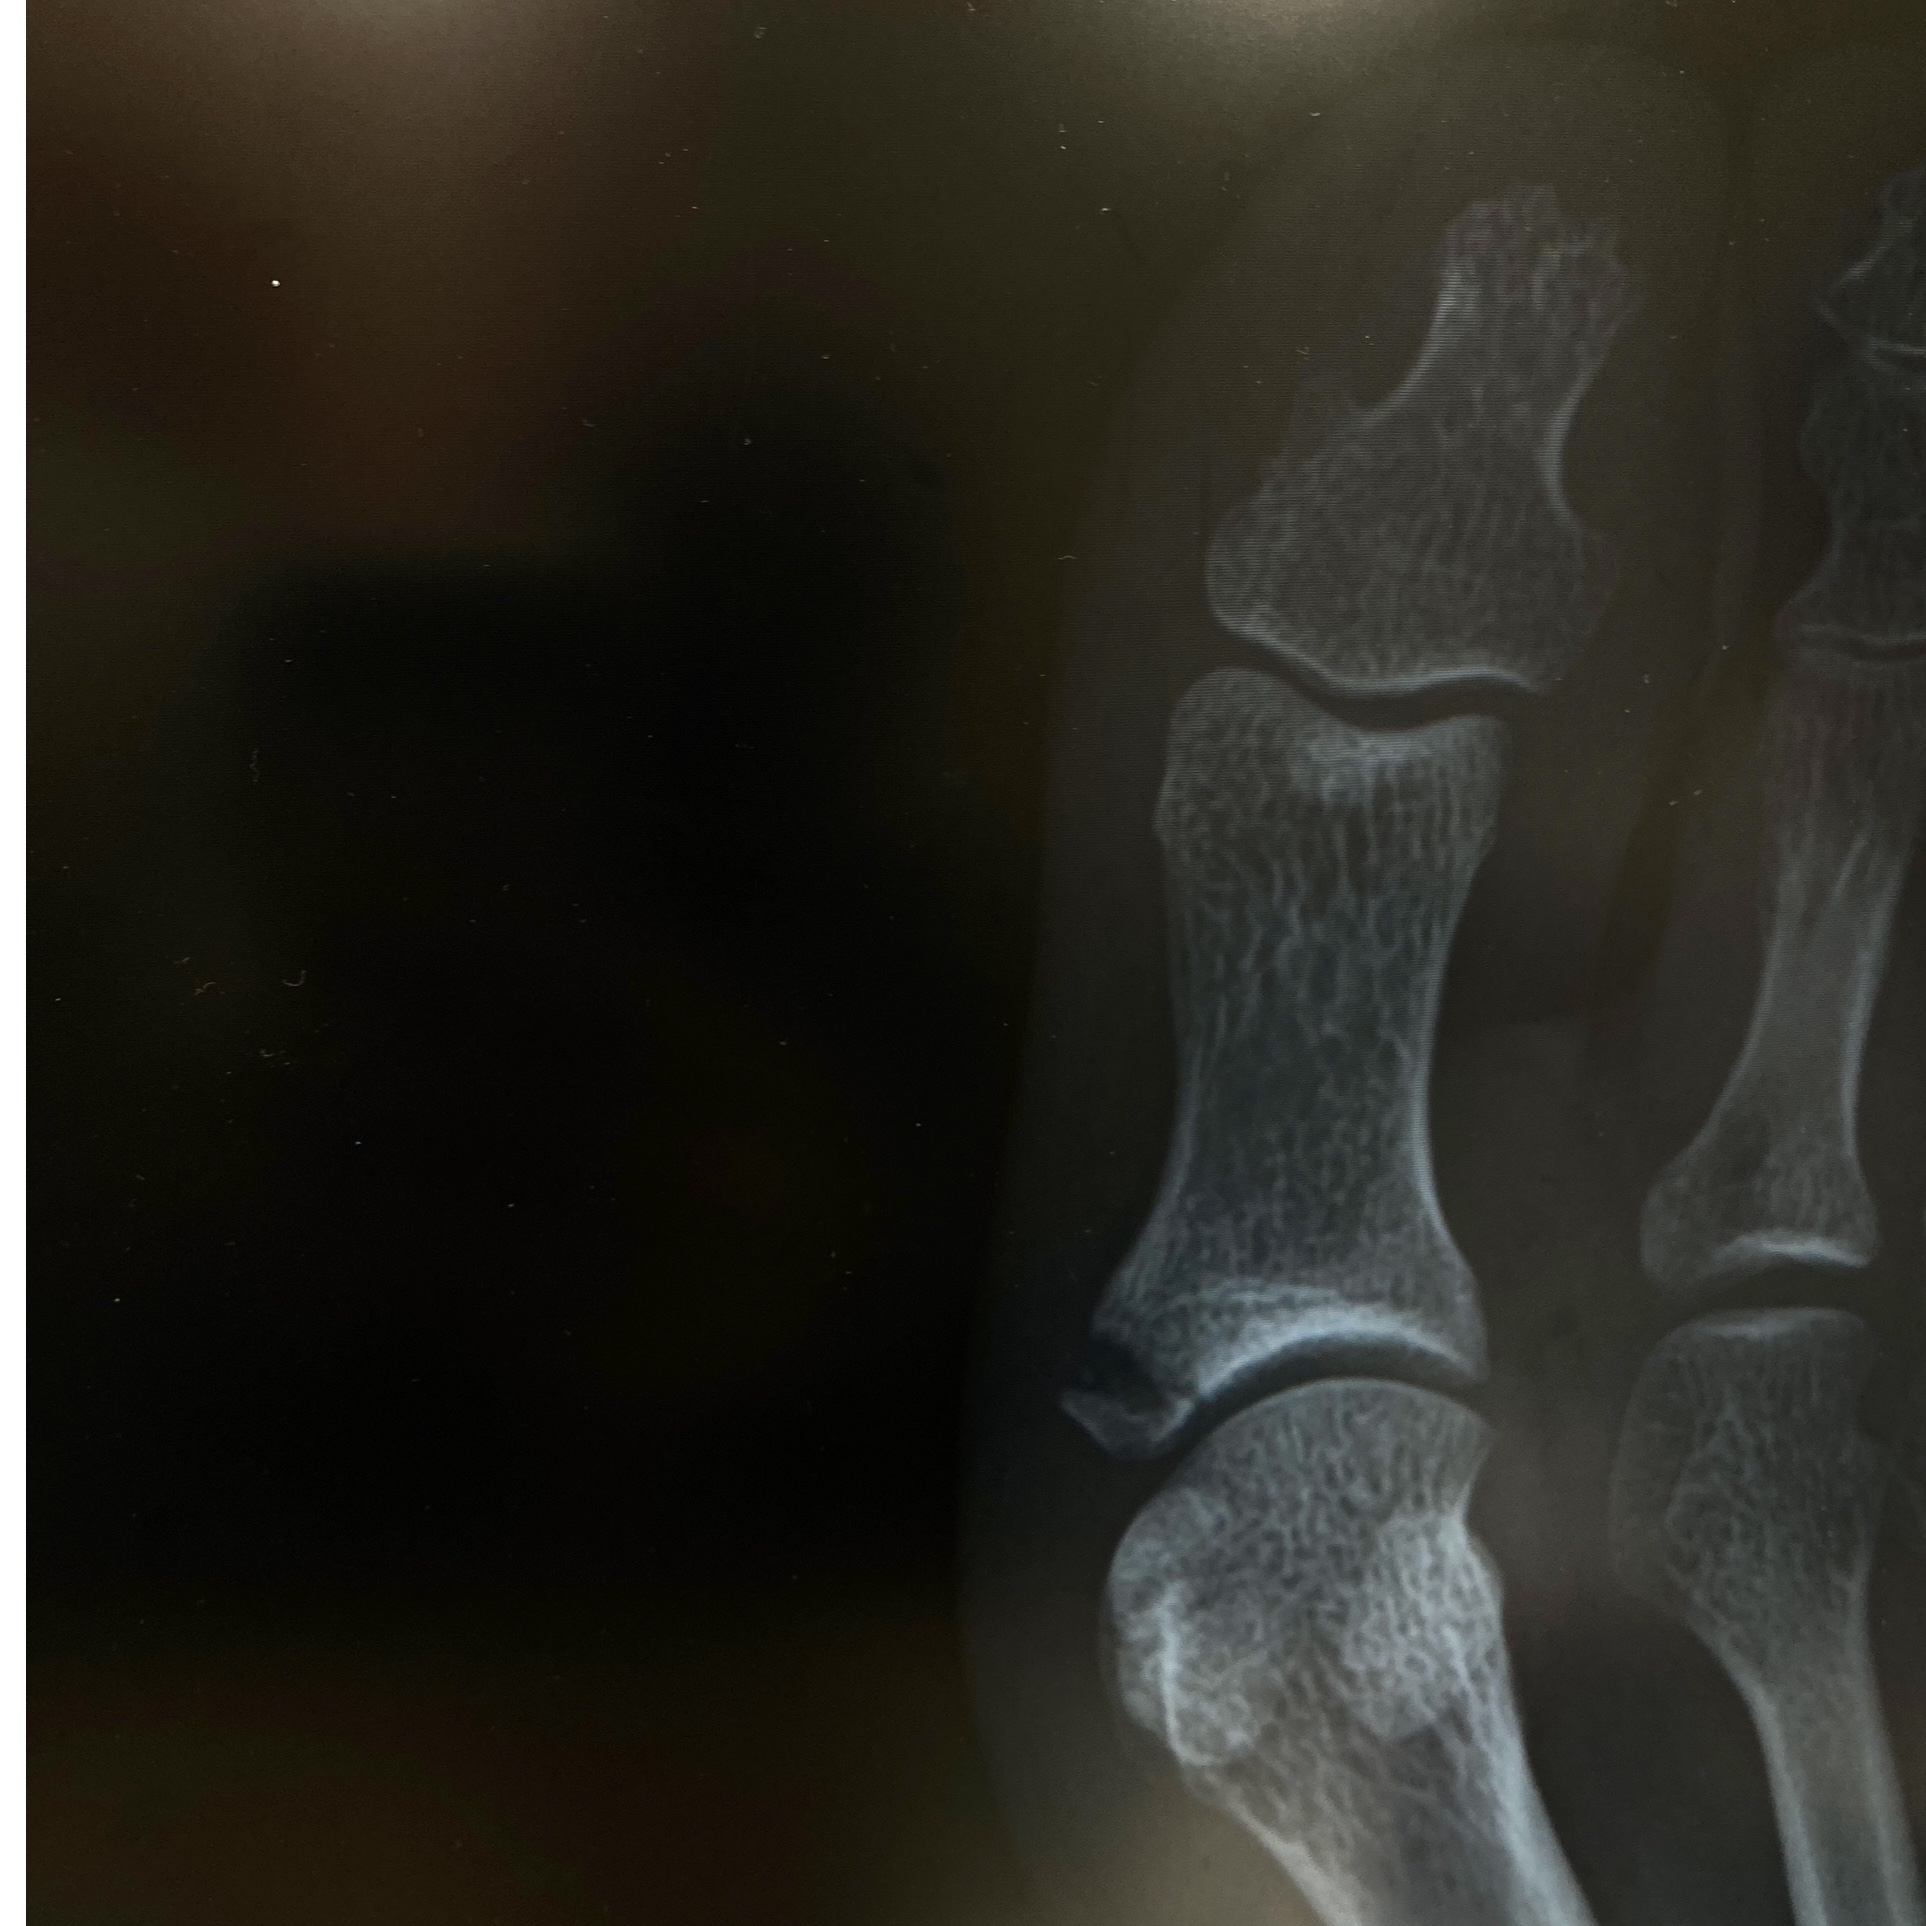

いやーまさか骨折してるとは思いもしませんでした。

足の親指側の骨なんですが

なんの需要もないけどレントゲンこっそり貼っときますww

誰が見てもパキッと割れてるー!!